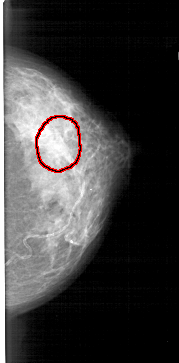

A_1447_1.RIGHT_CC

RIGHT_CC LINES 5071 PIXELS_PER_LINE 2506 BITS_PER_PIXEL 12 RESOLUTION 43.5 OVERLAY

FILE: A_1447_1.RIGHT_CC.OVERLAY

TOTAL_ABNORMALITIES 1

ABNORMALITY 1

LESION_TYPE MASS SHAPE LOBULATED MARGINS OBSCURED

ASSESSMENT 3

SUBTLETY 1

PATHOLOGY BENIGN

TOTAL_OUTLINES 1

BOUNDARY